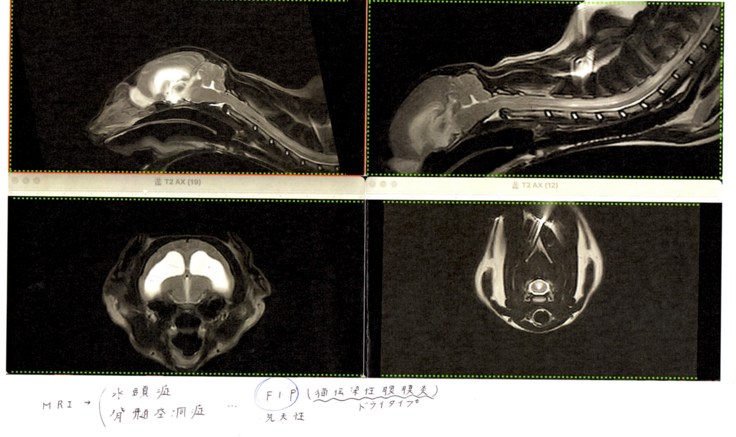

2日後、C病院で一通り説明を受け、全身麻酔でMRIの撮影を行いました。

結果は水頭症。原因が先天性脊髄空洞症かFIP(猫伝染腹膜炎)かどちらかまでがわからないと伝えられました。

脳ヘルニアもあり脳脊髄液を取ることが難しく確定診断ができないとのことでした。

現在ステロイドで調子が良いこと、その他にFIPの症状がとくに出ていないことを踏まえ、しばらくはステロイドと利尿剤で少し様子をみてもいいのではないかとお話がありその方針で治療を進めることにしました。

そちらで再度血液検査や超音波検査をし総合的に判断したところFIPドライタイプとなり注射+投薬治療を始めることとなりました。